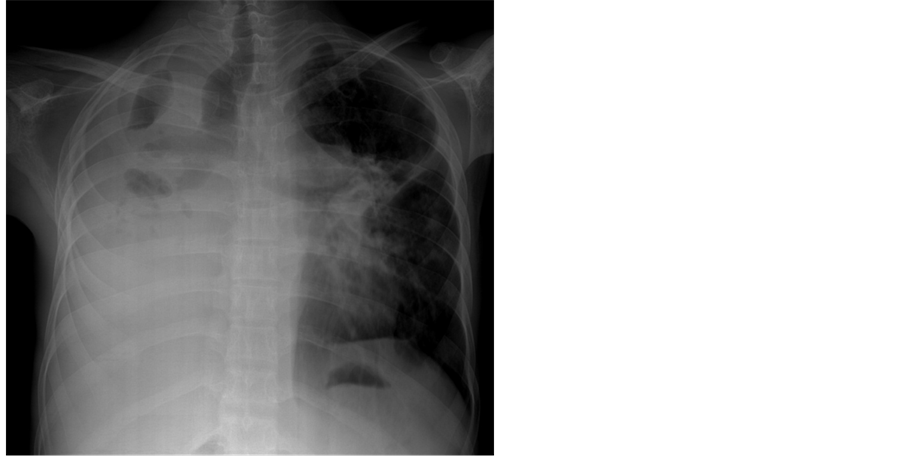

pressure 100/70 mmHg. Auscultation revealed diminished breath sounds on the right side of the chest with a dull note on percussion and a loud P2 (pulmonic component of second heart sound) with grade 2/6 soft systolic murmur over the lower left sternal border which increases in intensity with deep inspiration (Carvallo’s sign) suggesting tricuspid regurgitation. ECG revealed no arrhythmias and X-ray chest showed right- sided pleural effusion and extensive calcification over the cardiac shadow as shown in Figure 9. Transthoracic echocardiography revealed apical fibrosis of right ventricle, moderate pericardial effusion, right atrial dilatation as shown in Figure 10 and Figure 12, suggesting right ventricular endomyocardial fibrosis and severe tricuspid regurgitation as in Figure 11, Figure 13 and Figure 14 indicates coexisting pulmonary hypertension due to pulmonary damage caused by tuberculosis as shown in Figure 13 and free RV outflow tract as in Figure 15. Patient was treated with antituberculous drugs, antifailure measures such as digoxin and diuretics, ascites fluid tapping and antibiotics. He showed mild improvement in his symptoms.

Figure 9. X-ray chest PA (postero-anterior) view showing right-sided pleural effusion and endocardial calcification over the left ventricle in burn-out stage of EMF (endomyocardial fibrosis). ( [18] , Figure 2―left sided pleural effusion; [24] , Figure 2(a); [25] , Figure 2(c)).

Endocardial calcific deposits can be present, involving diffuse areas of the ventricles and Cockshott et al. described this feature in 1967. Calcification, an impressive finding on imaging denotes a burnt-out phase of endomyocardial fibrosis (EMF) and confirming the malignant nature of the disease. Chest X-rays show varying degrees of cardiomegaly and at times typical endocardial calcifications in the left and right ventricles as shown in Figure 9 (left ventricular endocardial calcification) ( [24] , Figure 2(a)) and in Figure 16 (right ventricular endocardial calcification) ( [25] , Figure 2(c) shows calcification in both ventricles) [26] .